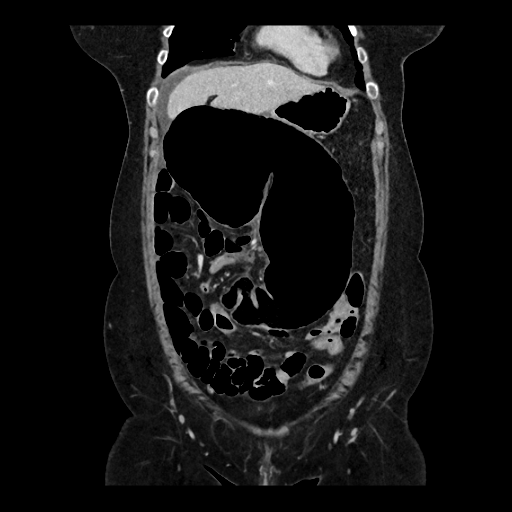

Une patiente de 59 ans, avec antécédents de lithiases vésiculaires, se présente aux urgences pour une douleur abdominale diffuse à type de colique, d'apparition brutale depuis la veille au soir. La douleur est d'intensité 8/10, sans position antalgique ni caractère transfixiant. La patiente signale que ces douleurs sont similaires à ses épisodes antérieurs de migration lithiasique biliaire. Le tableau clinique est également marqué par des nausées, six vomissements liquidiens et un vomissement biliaire à l'admission. La patiente note une inappétence ainsi qu'un épisode de selles liquides la veille. Ses antécédents chirurgicaux se limitent à une césarienne. A l'examen, la patiente est très inconfortable sans position antalgique, et afébrile (36,7°C). Les constantes vitales sont stables (TA 100/71 mm Hg, FC 83 bpm, FR 16 cycles/min, SpO2 95%). L'abdomen est souple, sensible en sus-pubien et épigastrique avec masse palpable sans défense ni détente. Les signes de Murphy et du psoas sont négatifs. Le bilan biologique révèle une légère hyperleucocytose (11,4 G/L) et une CRP à 6,8 mg/L, avec tests hépatiques normaux et des lactates à 1,2 mmol/L.

Quelle est la particularité évolutive du volvulus du cæcum par rapport aux autres types de volvulus coliques ?